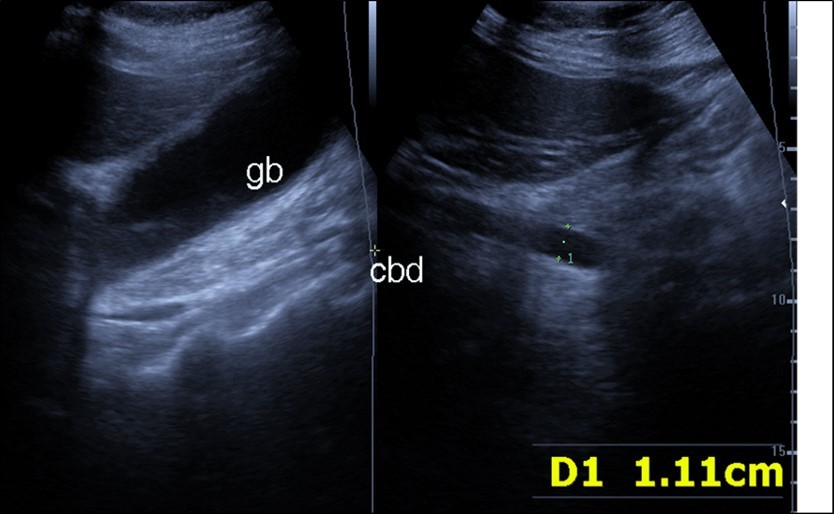

Abdominal ultrasound may revealed any of the followings:-Mild hepatomegaly with echogenic parenchyma and ascites in cases with hepatic impairment (Figure 4, Figure 5) ,thick walls of gall bladder with mildly dilated Common bile duct suggesting of biliary stasis and cholecystitis (Figure 6) .Abnormal renal echogenicity (Figure 7), suprarenal gland enlargements with heterogeneous texture ,splenic wedge shape area of hypoechogenicity ,thickened walls of bowel mainly the rectosigmoid region ,dilated bowel loops with free peritoneal fluid, and gases in the bowel wall with mesenteric and portal vein gases suggesting of bowel wall infarction13.

Figure 4.Real time ultrasound showing thickened wall of gall bladder (gb) with dilated Common bile duct (cbd) in patient with severe Covid-19.